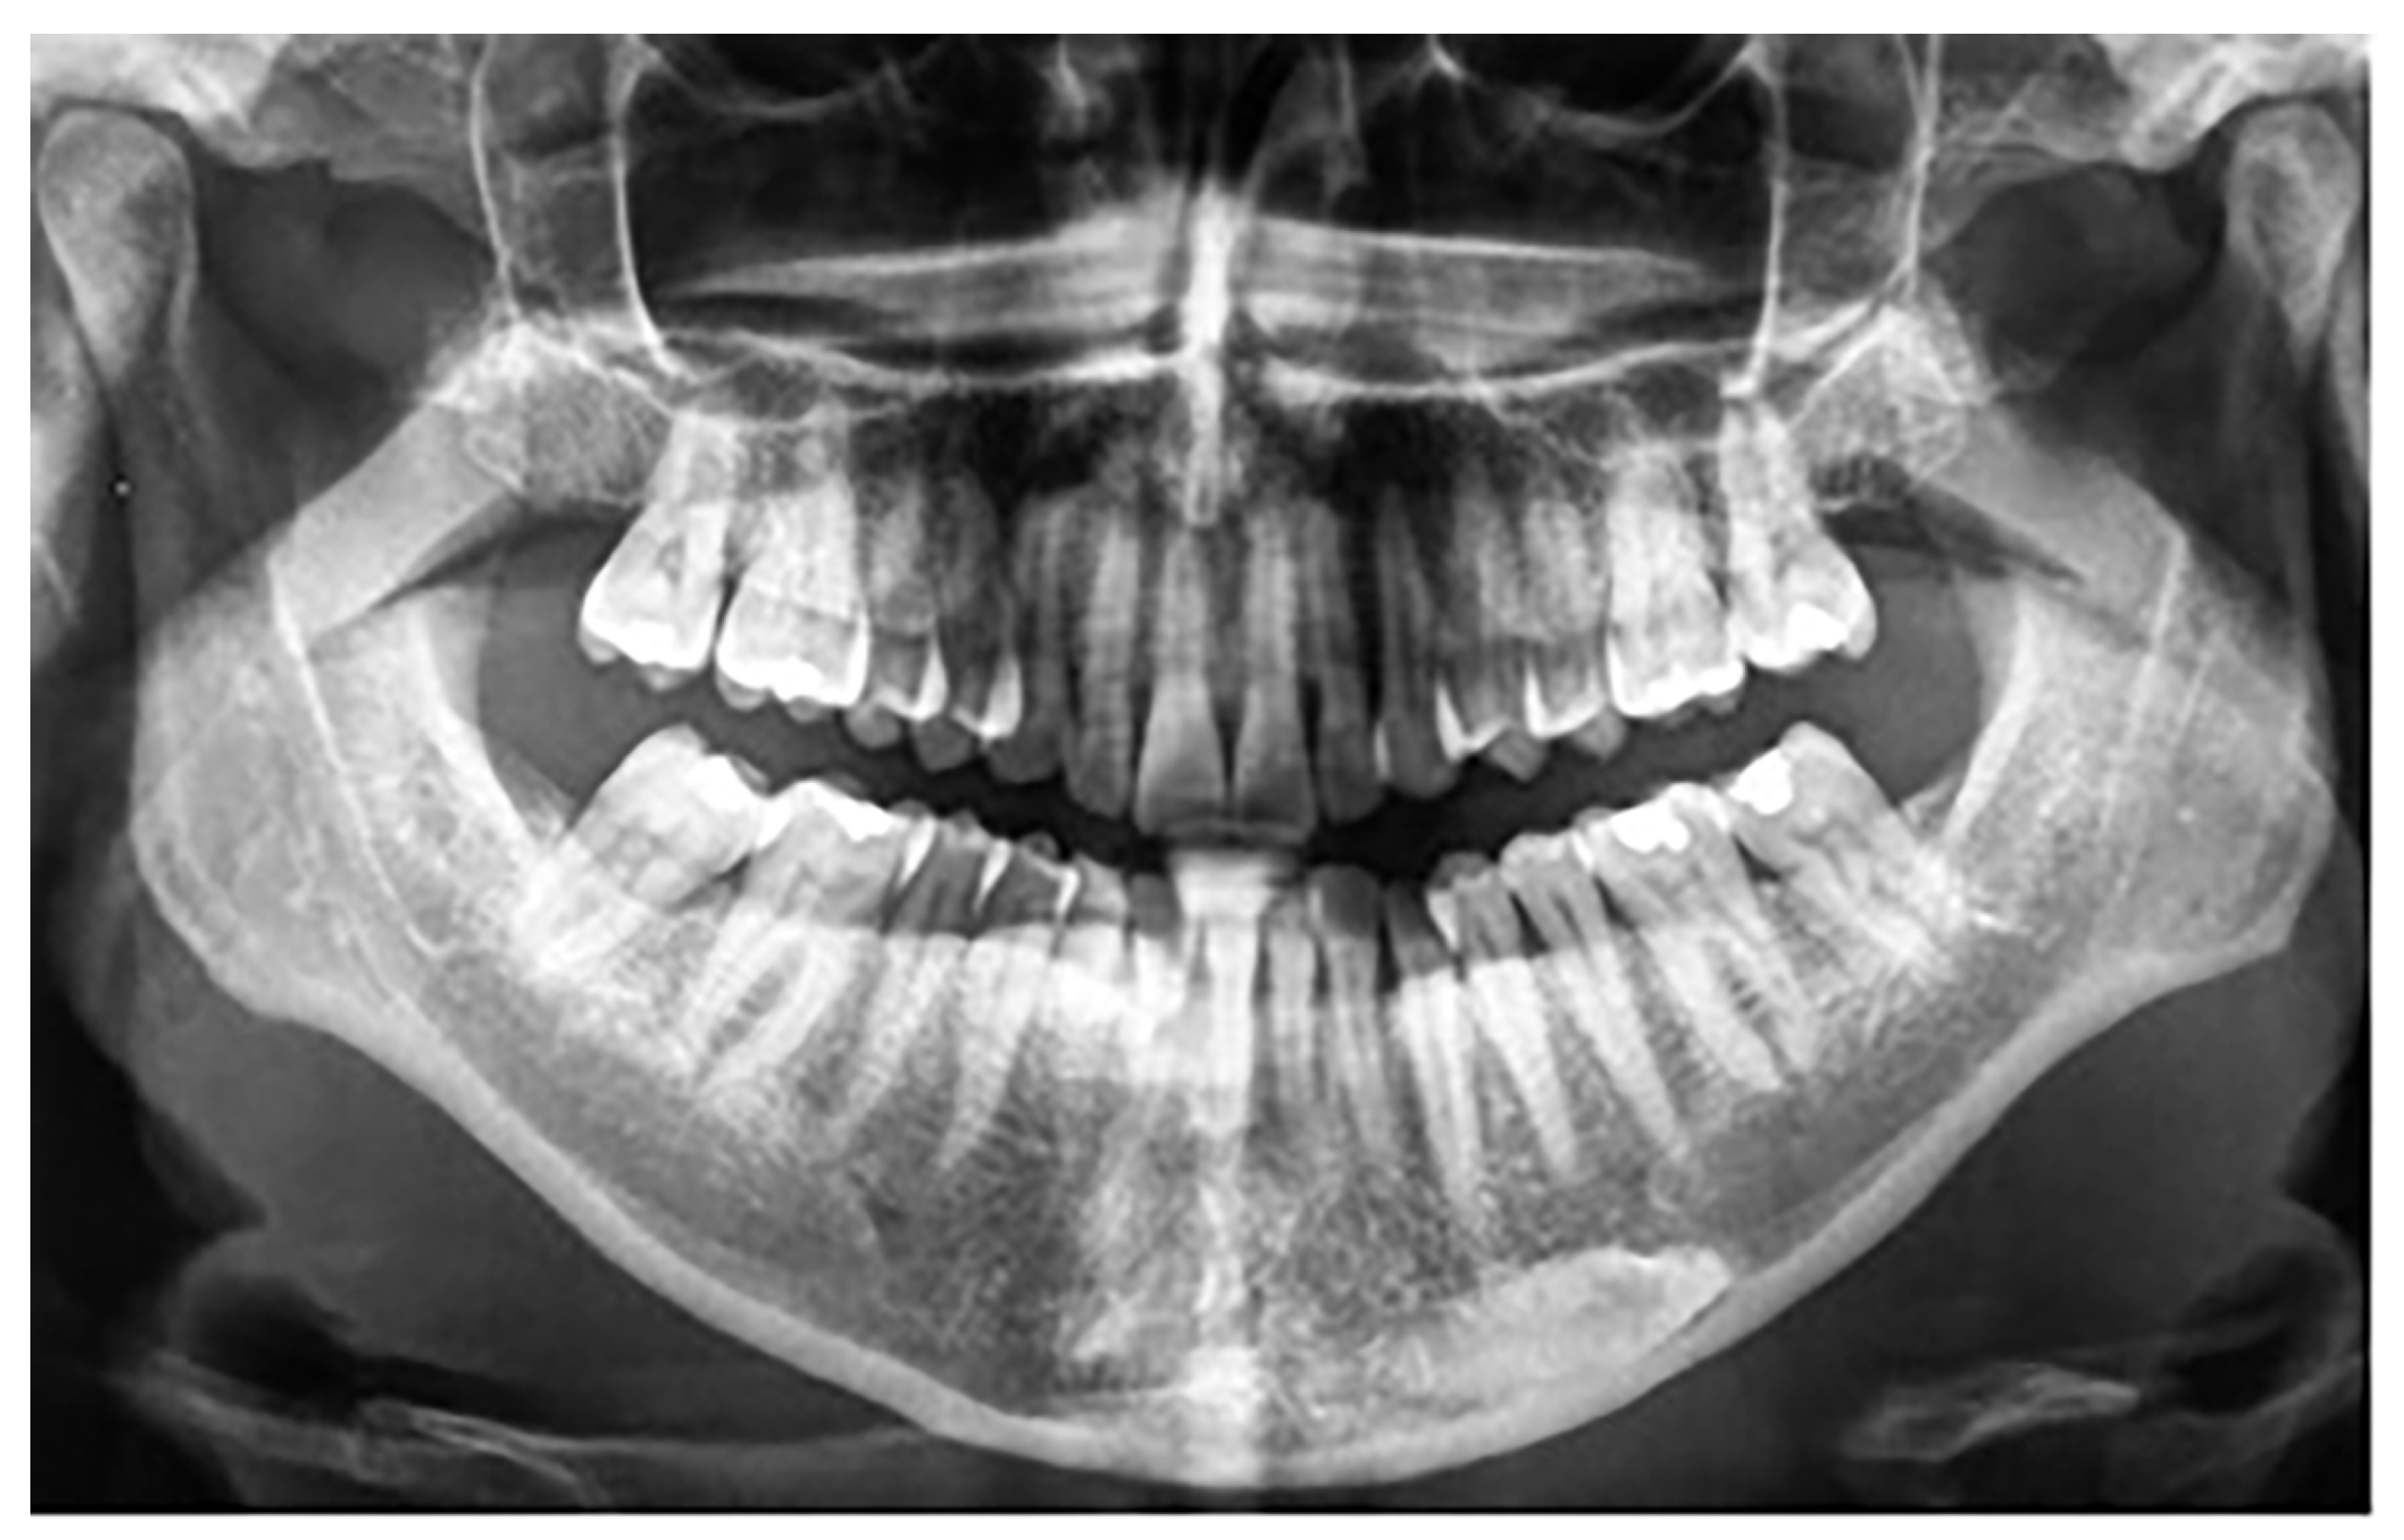

Figure 4.

Patient with impaction of mandibular canines and retained deciduous canines.

In group B, a total of 13 patients were found to have mandibular canine impaction. Impaction of the canines was bilateral in 1 patient and unilateral in 12 patients, for a total of 14 impacted permanent mandibular canine teeth. Four patients still had retained deciduous canines at the time of diagnosis (Figure 4). In two cases, the impacted canines were transposed in the region of the lateral incisors. Besides these 13 patients with impacted mandibular canines, one (female) of the 640 participants was found to have mandibular canine transmigration. The transmigration was unilateral. In this patient, the primary canine was retained. None of the patients had traumatic episodes, and none of them had systemic disorders. All the patients were asymptomatic.